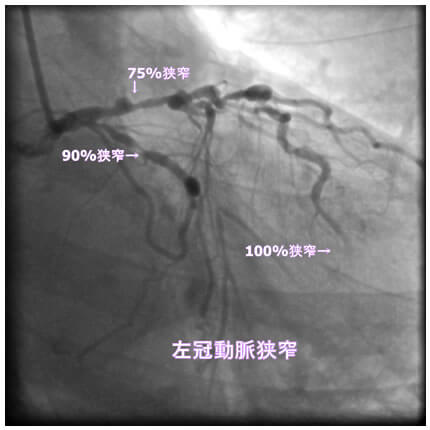

1番目の患者さんは80歳の男性です。この方の危険因子は高血圧、高脂血症、喫煙です。この方の冠動脈造影と腹部CT画像を示します。図1-1から1-8の画像は全て全てこの患者さんの画像です。

図1-2 左冠動脈造影像

よく解らないと思いますが、冠動脈に多数の狭窄があることと冠動脈が「こぶ状変化(医学用語で瘤状変化)」を生じているのが解ると思います。

参考までに、これを医学記号で表すと、下記のようになります。

「#1: 50% #2 :50% #3 #4PD #4AV:75% #5 50% #6 75% #7 75% #8 #9 #10 #11 #12 」

#1 、#2 などの数字は冠動脈の部位を表します。50%というのは正常の50%が狭窄しているという意味です。